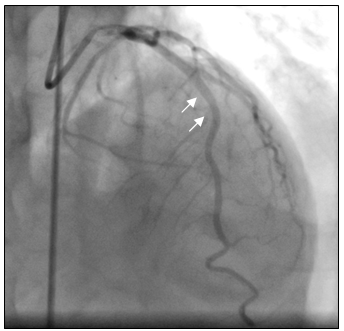

Tại phòng thông tim huyết áp bệnh nhân thấp 80/60mmHg nên chúng tôi không dùng Nitroglycerin. Sau khi chụp thấy hẹp nặng lan tỏa ở cả ba nhánh của động mạch vành, không loại trừ do co thắt nên chúng tôi đã tiến hành bơm 500µg Nitroglycerin vào động mạch vành. Kết quả chụp lại hiện tượng trên hoàn toàn biến mất, động mạch vành phải và trái thâm nhiễm nhẹ nhưng đều có kích thước lớn hơn nhiều so với ban đầu, dòng chảy TIMI 3 (hình 3a-3b), đồng thời huyết áp của bệnh nhân cũng cải thiện rõ 120/80 mmHg.

Hình 3a: Nhánh LCX, OM và LAD sau khi bơm Nitroglycerin

Hình 3b: Nhánh RCA sau khi bơm Nitroglycerin.